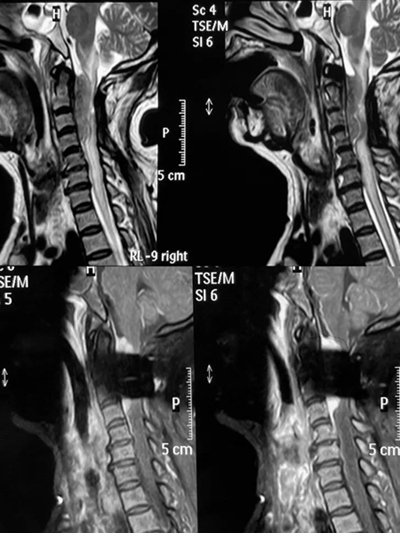

术前核磁检查显示颈1-4椎管内占位,脊髓受压严重